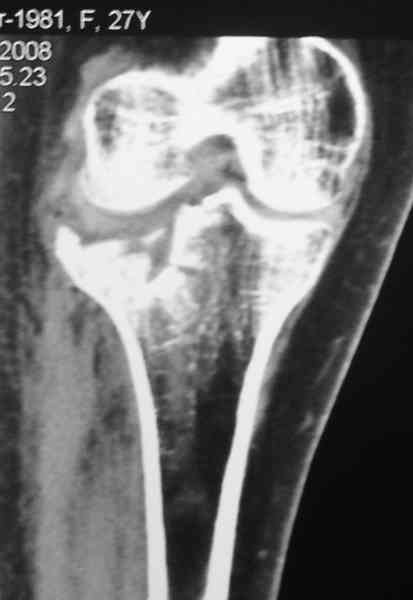

По тактике лечения, более импонирует второй вариант, но наружная плато расколота и туда при нагрузке внедряется н/мышелка бедра, поэтому после дистракции как репонирвать: или стяжными винтами, или изогнутами спицами или субхондральная костная пластика?

Уважаемый Абдурашид. Если нет противопоказаний , то из оперативных способов, я бы рекомендовал следующие: Полное замещение наружного мыщелка аллотрансплантатом либо открытая репозиция с элевацией и замещение дефекта ауто или аллокостью. В Ваших условиях , я бы рекомендовал второй способ. Во-время элевации необходимо разъединить фрагменты со стороны сустава ( надсечь скальпелем по линиям перелома, а затем тонким остеотомом их разъединить. При помощи долота произвести неполную остеотомию ( захватите не менее 1,5 - 2 см губчатой кости и поднять фрагменты, визуально отрепонировать и фиксировать 2-3 спицами. Дефект заместить костным ауто или аллатрансплантатом. Окончательная стабилизация пластиной ( лучше с угловой стабильностью, либо АВФ - позволит спокойно устранить угловую деформацию.